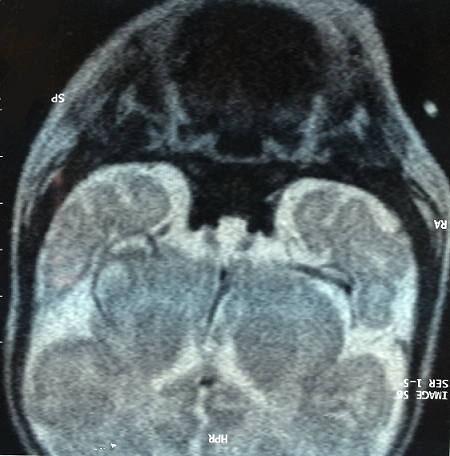

Arachnoidocele is characterized by the herniation of the subarachnoid space within the sella turcica, associated with some degree of flattening of the pituitary gland. In children and adolescents, Arachnoidocele is rare, and the clinical picture is much less benign, with an increase in familial incidence, associated skeletal disorders, and endocrine abnormalities. OH was in infant admitted at the age of one month for respiratory symptoms. The examination on admission found an hypothermic infant with macroglossia, an anterior and posterior fontanelle wide, an umbilical hernia with growth retardation and normal cranial perimeter. Her height was 3200 g and her weight was 52 cm. The examination of others systems was unremarkable. She had central hypothyroidism (FT4 below 0.4 and TSH equal to 0.346). An exploration of the pituitary was requested, finding an achievement of the cortical axis revealed by the occurrence of multiple episodes of hypoglycemia with normal insulinemia and normal Adreno-Cortico-Trophic-Hormone with low cortisolemia (52 nmol/l). Growth stimulation tests were performed. Growth hormone levels were less than 10 ng/ml. A brain MRI was applied for a arachnoidocele intra-sellar repressing anterior pituitary with an anterior pituitary parenchyma very small without abnormality posterior pituitary or pituitary stalk.The patient was treated with hydrocortisone, levothyroxine and growth hormone replacement. The outcome was favorable without recourse to neurosurgery at the lack of damage to the optic nerve and the sphenoid bone, with a decline of five years otherwise the child has a delay in psychomotor acquisitions.